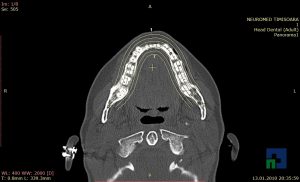

În cazul traumatismelor cranio-cerebrale:

- Diagnosticul edemului cerebral, a contuziei cerebrale, a leziunilor axonale difuze edematoase/hemoragice, a dilacerării cerebrale, a hematomului intraparenchimatos posttraumatic, a hematoamelor subdurale/extradurale (acute, subacute, cronice), a hemoragiei intraventriculare, a hemoragiei subarahnoidiene

- Diagnosticul traumatismelor de bază de craniu

- Diagnosticul fracturilor: